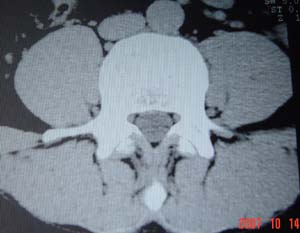

1.l4~5间盘膨出伴突出(中央型)

2.l5-s1后纵韧带钙化.

测量应该测上一层面,。支持诊断。